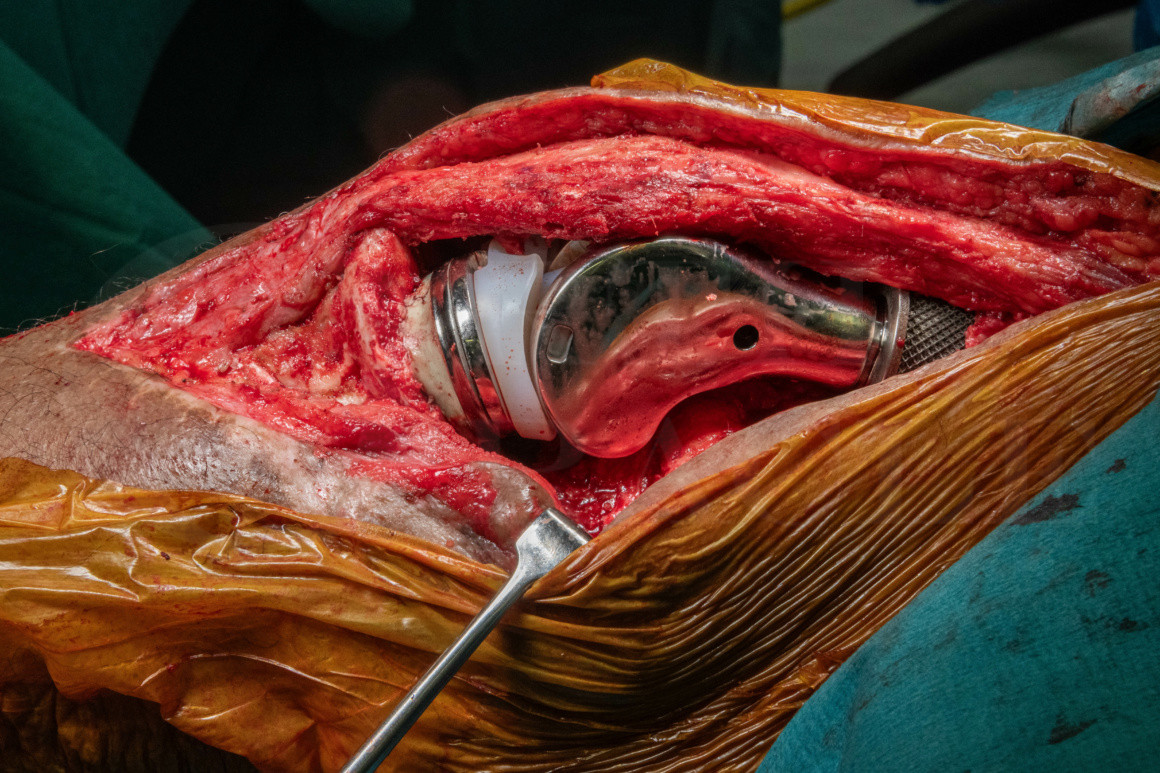

El Hospital de Ortopedia de la Unidad Médica de Alta Especialidad "Dr. Victorio de la Fuente Narváez" dio a conocer la realización de su primera artroplastia total de rodilla asistida por robot, una técnica que busca mejorar la precisión de la cirugía y facilitar la recuperación de los pacientes.

A diferencia del procedimiento tradicional, el sistema robótico permite realizar cortes más precisos en el hueso mediante un software que guía al cirujano en tiempo real.

Esto ayuda a colocar los implantes con mayor exactitud y a lograr una alineación personalizada, ajustada a la anatomía de cada paciente.